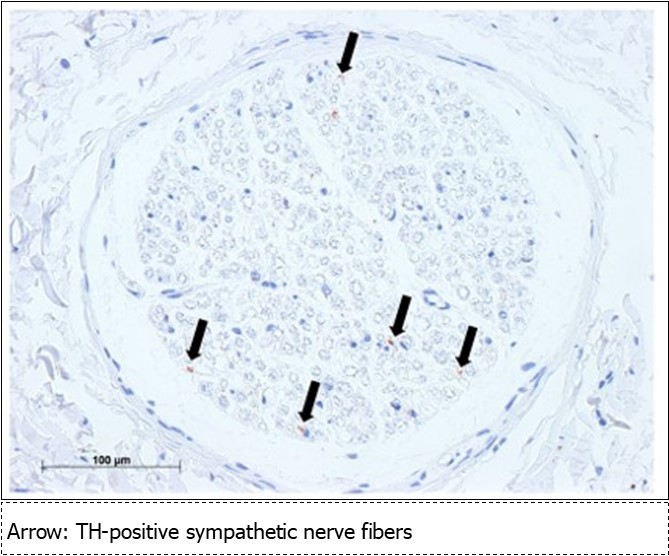

Based on the results obtained in this study, the mental nerve and the marginal mandibular branch of the facial nerve are completely fused at the perineurium. Most nerve diagrams indicate that the mental nerve is only a sensory nerve, and that the marginal mandibular branch of the facial nerve is a pure motor nerve. However, we found that there is a need for autonomic nerves to be present in the lower face region, where there are salivary glands and sweat glands, including the lower lip and chin (the regions of these nerves). Hence, we aimed to determine where these nerves originate. In the present study, we observed that the vasomotor nerve of the facial artery branched off from the buccal branch and the marginal mandibular branch of the facial nerve (Figure 2※), and we identified the fact that there are sympathetic and parasympathetic fibers in the facial nerve. This was also confirmed micro-anatomically. Figure 5 shows a cross-section of the optic nerve, and Figure 6 shows a cross-section of the mental foramen region of the mandibular nerve. Tyrosine hydroxylase immunostaining stained the sympathetic nerves (provided by lecturer Masahito Yamamoto of the Department of Anatomy, Tokyo Dental College). The trigeminal nerve includes sympathetic fibers, and when the two sections are compared, the optic nerve has a substantial number of such fibers, whereas the mandibular nerve has very few. Matsubayashi 10 wrote extensively on this issue. It is known that the trigeminal nerve, which is the great auricular nerve, auriculotemporal nerve, and zygomatic branch of the facial nerve, consists of cutaneous nerves of the face and sympathetic nerve fibers, although there are few sympathetic nerve fibers in the maxillary nerve or mandibular nerve.

Figure 6.Sympathetic nerve fibers of the mandibular nerve (mental nerve: TH staining) Bar = 100um

There are few sympathetic nerves in the mental foramen region of the mandibular nerve (Figure 6, Matusbayashi et al. 10).